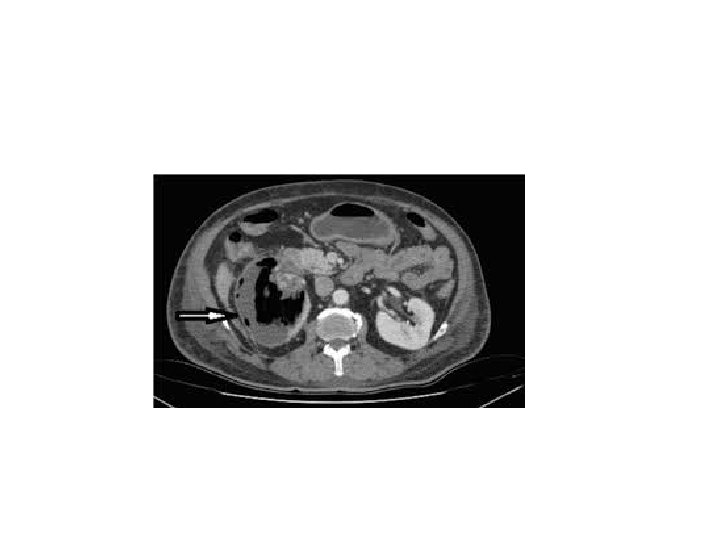

Ct scan with contrast showing renal abscess with ring sign(rim enhancement)

• The most common presenting symptoms in patients with renal/perinephric abscesses include fever, flank or abdominal pain, chills, and dysuria. Many of the symptoms have lasted for more than 2 weeks • The appropriate management of renal abscess must first include appropriate antibiotic therapy, percutaneous drainage under CT scan or ultrasound guidance, drainage of obstruction if found.